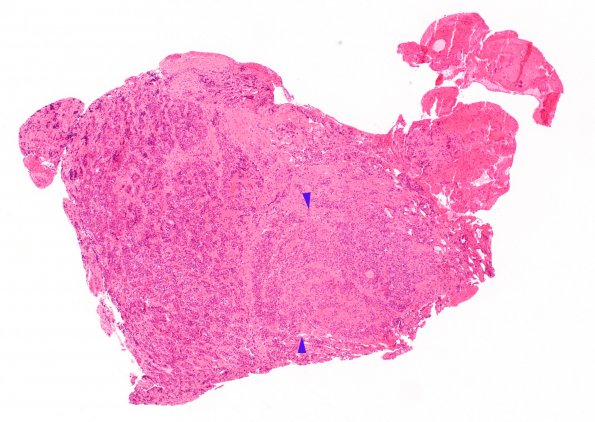

Case 16 History ---- [54yo female presenting with Cushing's disease. MRI showed a 0.8 cm post-contrast enhancing mass in the sella.] ---- 16A1 H&E stained sections of the pituitary show this fragment of anterior adenohypophysis which appears rather unremarkable in architecture but, at higher magnification, exhibits Crooke's hyaline change. There is a single focus of tissue that has a nodular appearance (between arrowheads) which represents a microadenoma, as shown in the subsequent studies.